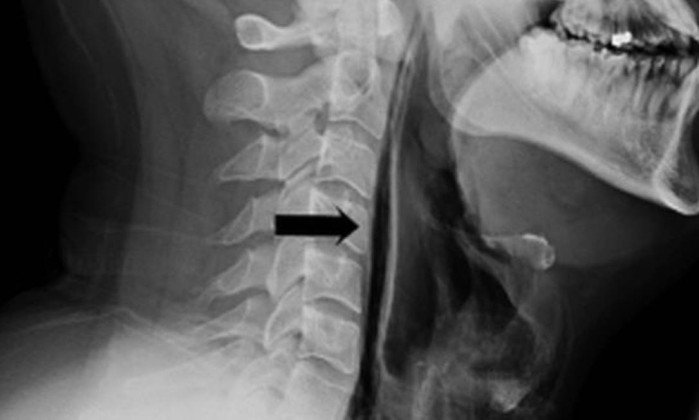

O paciente percebeu os sintomas após impedir um espirro apertando o nariz e fechando a boca. Como consequência, sofreu uma fratura grave na garganta. O caso foi surpreendente, segundo médicos que atenderam o homem, porque a ruptura da parte de trás da garganta só é normalmente vista em episódios de traumas e acidentes.

Em um artigo publicado na última segunda-feira, pelo periódico científico "British Medical Journal Case Reports", médicos de Leicester descrevem o caso de um homem de 34 anos que chegou ao hospital relatando dificuldades de deglutição, além de uma "sensação de estalar" no pescoço, que estava inchado.